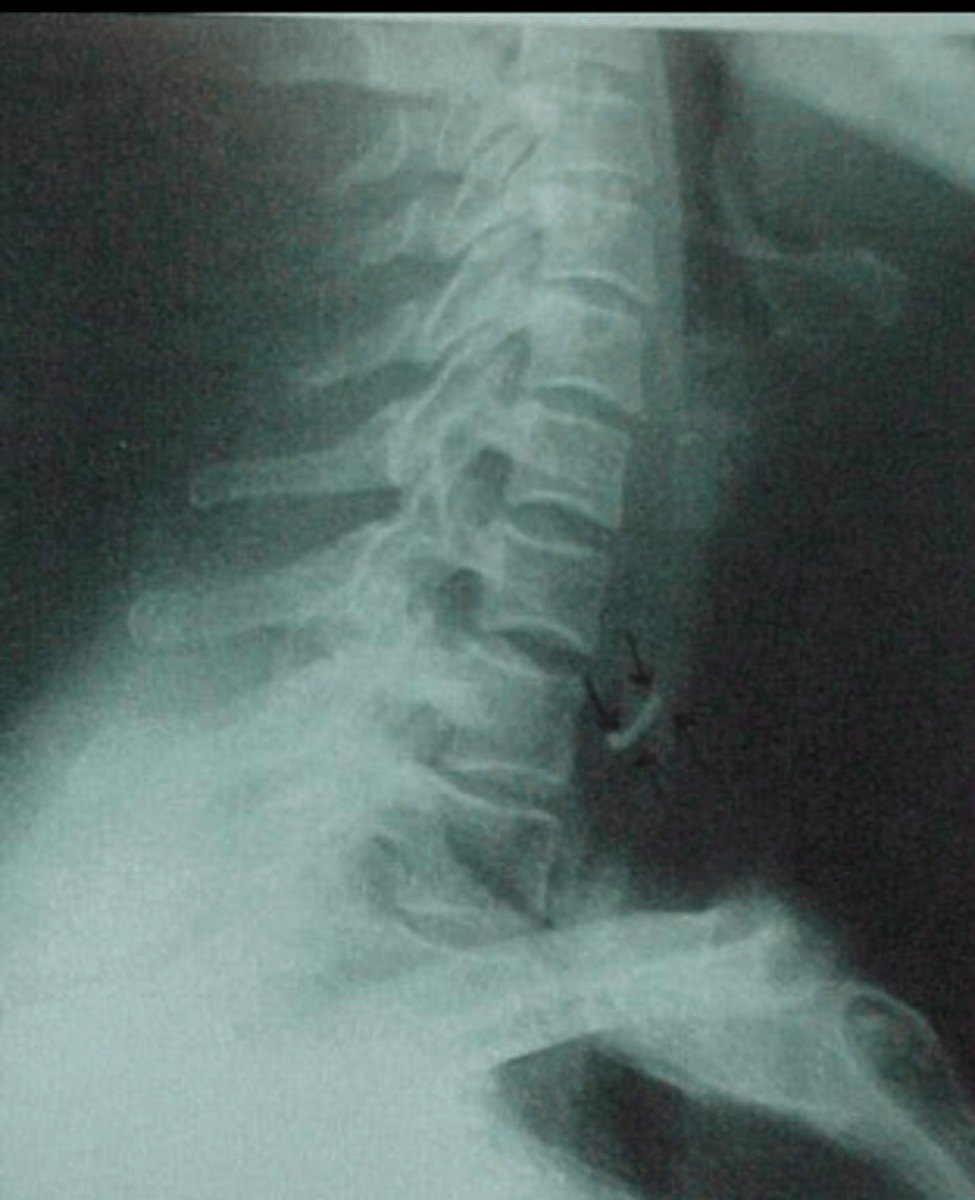

What views / projections should we do when plain imaging minor penetrating foreign bodies?

• AP/DP of affected area to include enough bony anatomy for confirmation of area

• Tangential view (modified views - to check how far the FB has penetrated into the soft tissue)

Gun shots could cause different types of appearances on radiographers based on the type of gun, speed of bullet, etc. :

• High velocity - shock wave, large exit wound

• Low velocity - no exit wound

• Fragment / Change shape on entry (mushrooming)

• Yawing (slows down and changes direction in tissue)

• Shotguns - low velocity but cause massive tissue damage